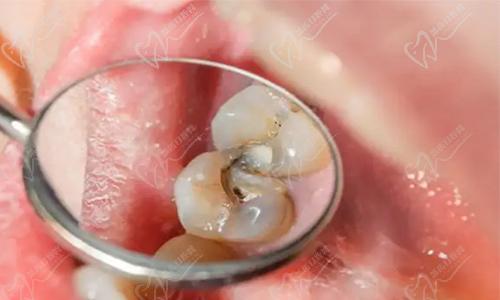

南京德牙联合口腔医院汇聚了一批经验十分丰富、技术高超的口腔医生,涵盖了口腔全科、口腔修复、口腔正畸、口腔种植、儿童口腔等多个专科。医院引进了高端的口腔诊疗设备,如数字化口腔CT、牙科显微镜、CAD/CAM等,为患者提供精细、微创、有效的诊疗方案。

南京德牙联合口腔医院引进了国内外高端的口腔诊疗设备,例如数字化口腔扫描仪、显微根管治疗仪等等。这些高端设备的应用,让诊疗过程更加精细、有效,也大大提升了患者的就诊体验。